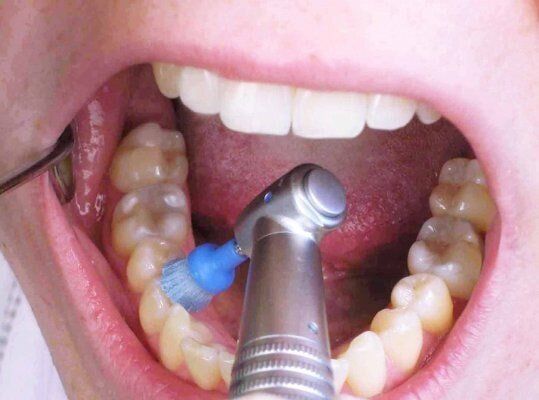

TEETH CLEANING & SCALING